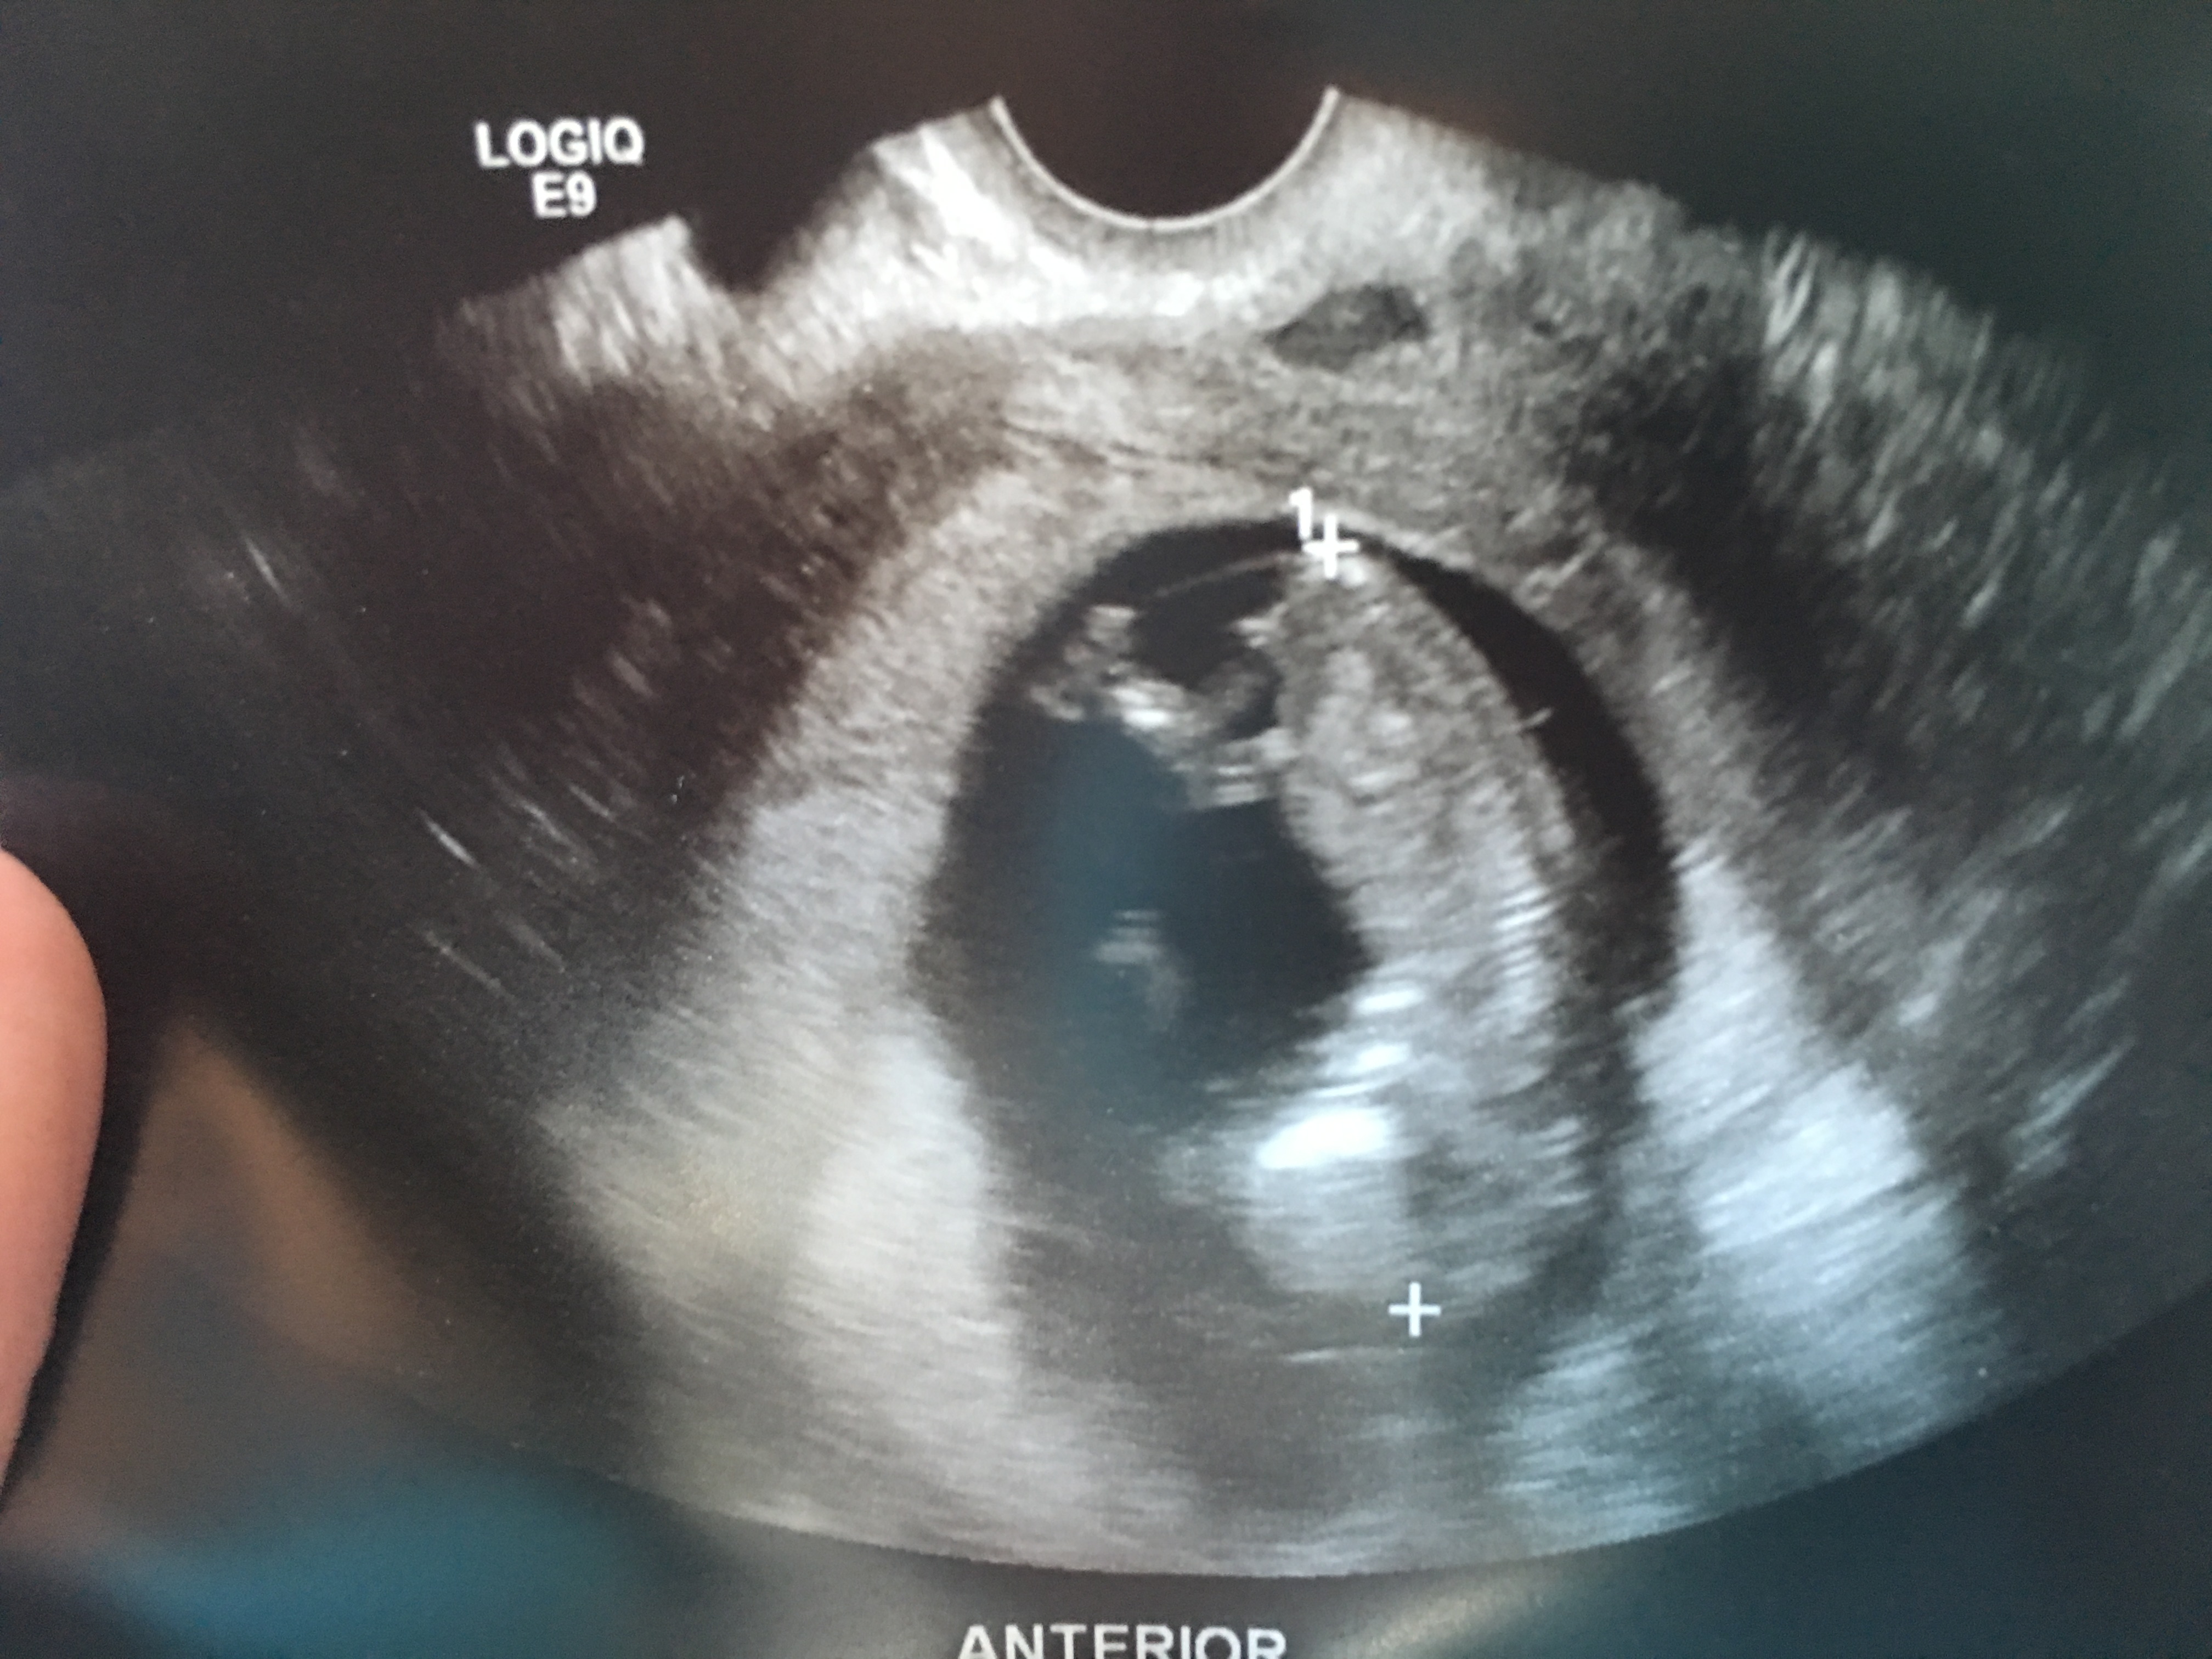

Any Guesses 11w6d